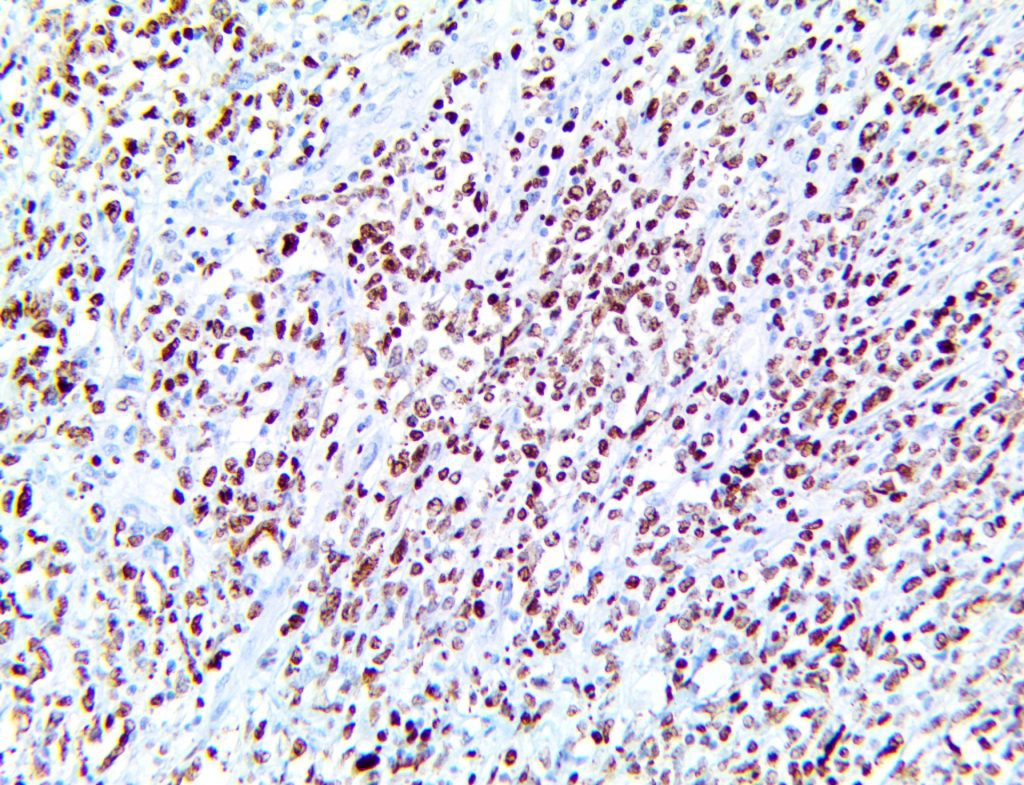

It is the ICU physician who is most likely to witness one of the deadliest manifestations of the abnormal immunological response, the cytokine storm syndrome (CSS). This response is also referred to by some as the cytokine release syndrome (CRS). CSS is characterized by continuous activation and expansion of macrophage and lymphocyte populations, which secrete large amounts of cytokines, causing the cytokine storm. This massive cytokine release is akin to hemophagocytic lymphohistiocytosis (HLH) disease, a syndrome characterized by initial unchecked and persistent activation of cytotoxic T lymphocytes and NK cells.

Clinical and laboratory manifestations of HLH include fever, enlarged liver and/or spleen, neurologic dysfunction, coagulopathy, liver dysfunction, cytopenias (i.e., low levels of erythrocytes, leukocytes, and/or platelets), hypertriglyceridemia, hyperferritinemia, hemophagocytosis, and eventually diminished NK cell activity as the immune system becomes progressively paralyzed. HLH can be familial (primary HLH) or secondary to another disease process (sHLH), such as rheumatic disease, in which it is referred to as macrophage activation syndrome (MAS, characterized by elevated ferritin).